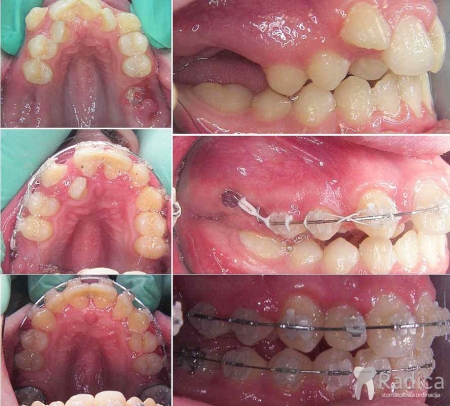

Izvlačenje impaktiranih očnjaka:

U sljedećem slučaju smo izvlačili oba gornja impaktirana očnjaka: